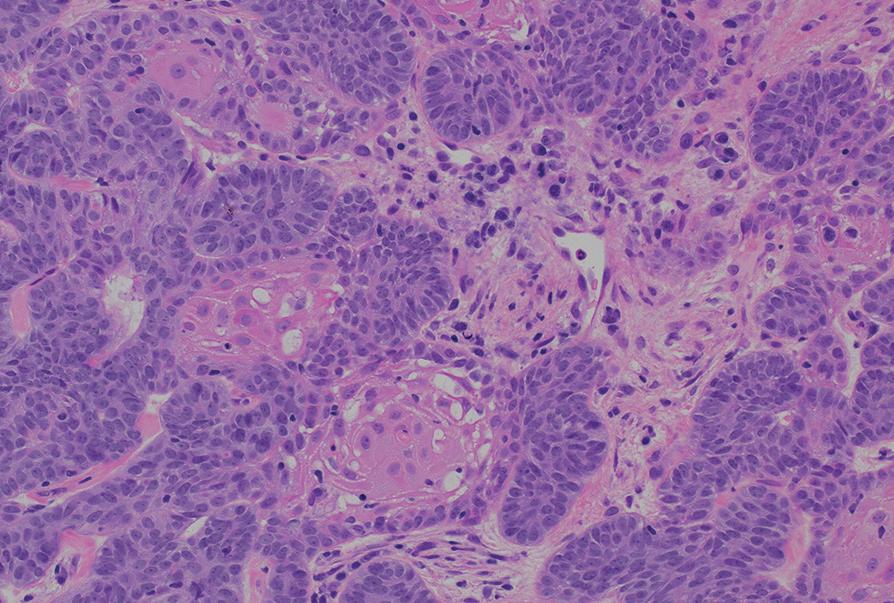

54 Oral Medicine, Oral Diagnosis, Oral Pathology

An unusual clinical and histopathologic presentation of a maxillofacial ameloblastoma: a literature review and case report

Pallavi Parashar

Clayton Davis